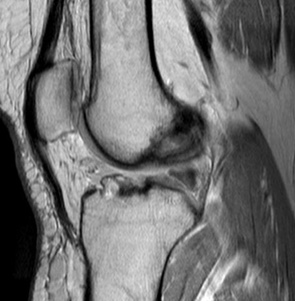

МРТ коленного сустава. Сагиттальная Т1-взвешенная МРТ. Нормальный ход трансплантата ПКС.

МРТ коленного сустава. Сагиттальная Т2-взвешенная МРТ. Разрыв трансплантата.